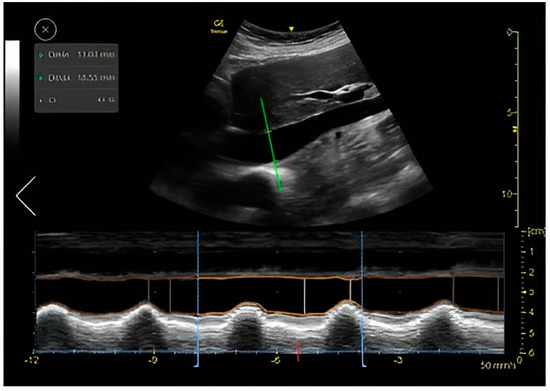

4. The IVC Collapsibility Measurement

The IVC clips were taken from the subcostal IVC view (Figure 3). In this view, the maximum and minimum diameters of the IVC throughout a respiratory cycle were measured two cm from the IVC-right atrium junction, using M-mode, providing the CI that represents the collapsibility of the IVC.

Following imaging acquisition, a post hoc analysis of the acquired IVC clip was performed in two different manners: (1) Using a real-time, machine-integrated, automatic IVC tool, and (2) by the expert physician, blinded to the automatic assessment, who examined the same clip frame-by-frame and measured the CI manually. The CI is presented as a percentage of the IVC collapsibility (minimal IVC size divided by the maximal IVC size).

Each IVC collapsibility measurement included the calculation of the Caval Index (CI), which is calculated as follows:

CI = maximal   expiratory   diameter + minimal   inspiratory   diameter maximal   expiratory   diameter

As mentioned, all clips were scored manually based on the quality of imaging from zero to two: 0—low, or failed attempt to track the IVC, or image that could not be analyzed, 1—CI can be measured and calculated but with moderate imaging quality and 2—for good quality clips with a clearly demonstrated IVC.

IVC CI Automatic Measuring Tool

The auto IVC tool automatically places the M-mode cursor 2–3 cm below the diaphragm. The algorithm then measures the maximum and minimum diameters of the IVC throughout a respiratory cycle (Figure 4). The auto IVC tool measures the maximum and minimum diameters of the IVC throughout the respiratory cycles in real time. The collapsibility index represents the collapsibility (diameter change) of the inferior vena cava between expiration and inspiration. The quality indicator is represented by the color of the M-mode cursor, and varies between green/yellow/red to represent excellent/average/unacceptable image quality, respectively.

Forty-six IVC clips acquired from 37 patients were included in the analysis. Patients were primarily males (62%), with a mean age of 60.45 ± 15.61 and a mean body mass index (BMI) of 26.98 ± 5.48 (Table 1). The mean collapsibility index (CI) was 0.30 when measured manually by an expert and 0.35 when measured by the automatic tool. The Intraclass Correlation Coefficient for agreement between the automatic and physician-assessed quantifications was low (kappa 0.388; p = 0.041). When analyzed from only high-quality acquired clips (grade 2), the Intraclass Correlation Coefficient rose to 0.536 (p = 0.009). When analyzed from only lower and medium quality acquired clips, the Intraclass Correlation Coefficient was negative (−1.314). When divided into two groups of collapsibility index, below and above 0.5, the Intraclass Correlation Coefficient for agreement between the automatic and physician-assessed quantifications was 0.536 (95% CI 0.009 sig) (Table 3). For the image quality agreement, we found a significant difference (p = 0.001, Fishers Exact test value—14.311, α) in the agreement of quality between the physicians’ group and the automatic tools group.

For IVC size and collapsibility index assessment, the tool was found to be very reliable with an agreement coefficient of 0.536 (95% CI, p = 0.009) when utilized on good IVC image quality and unreliable when utilized on medium and low image quality (Table 3). This is probably due to the technical challenge of measuring the diameter of the IVC when the vein borders are not clearly demonstrated and when there is variability in the placement of the M-mode cursor (Figure 4). We confirm that when the image quality of the IVC is good, this tool is reliable, and the automatic assessment of the IVC CI can be used.

Figure 3. Acquisition (probe point—green arrow) and anatomy of IVC View.

Figure 4. Auto IVC tool: auto marker placing, M-mode and data display.